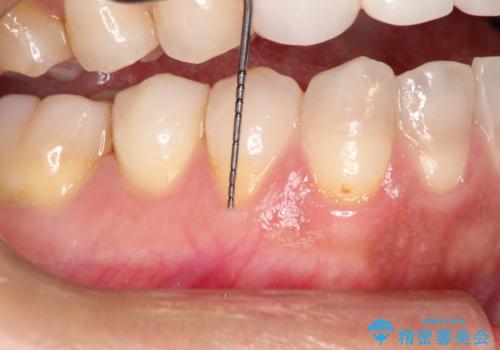

- 昔に受けた矯正治療がきっかけで歯肉が下がってしまった事を主訴として来院された患者様です。

結合組織移植術を行う方法を提案しましたが、傷口が口蓋にもできるのが嫌だとのことで、代替案としてバイオマテリアルを併用した根面被覆術を計画致しました。

治療対象部位は右下4,5,6番の3本です。